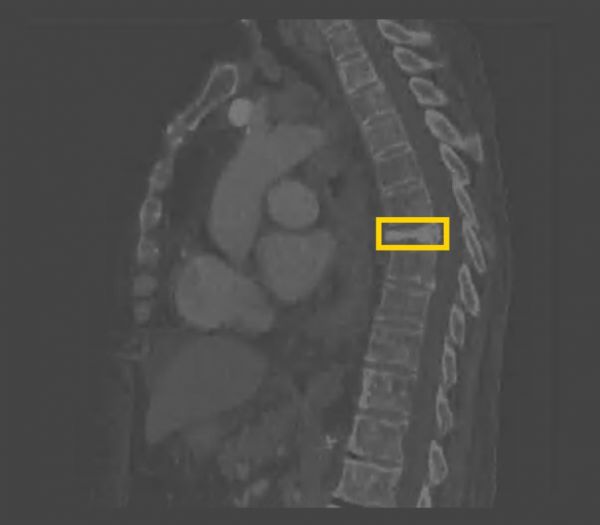

西门子的AI-Rad系统针对胸部CT影像,提供多方面的测量、定位和自动报告生成功能。比如,借助影像分割技术,找出胸部CT影像中大动脉的像素级定位,实现对动脉直径等多方面的自动化测量。该系统还利用目标检测技术,对体内器官的各项异常进行定位和初步诊断。

(AI-Rad系统,图片来自西门子)